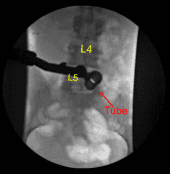

A 22-gauge spinal needle was used to localize the L5-S1 level. A marking pen was used to demarcate the midline. An 18 mm vertical incision adjacent to the spinous process on the right side was demarcated. 1% lidocaine with epinephrine was infused.

The skin was opened with a #15 blade scalpel. Hemostasis was obtained with Bovie. Bovie was used to sharply divide the fascia. Sequential dilators were used to dock a 16 mm diameter x 4 cm tubular retractor which was affixed rigidly to the bed frame.